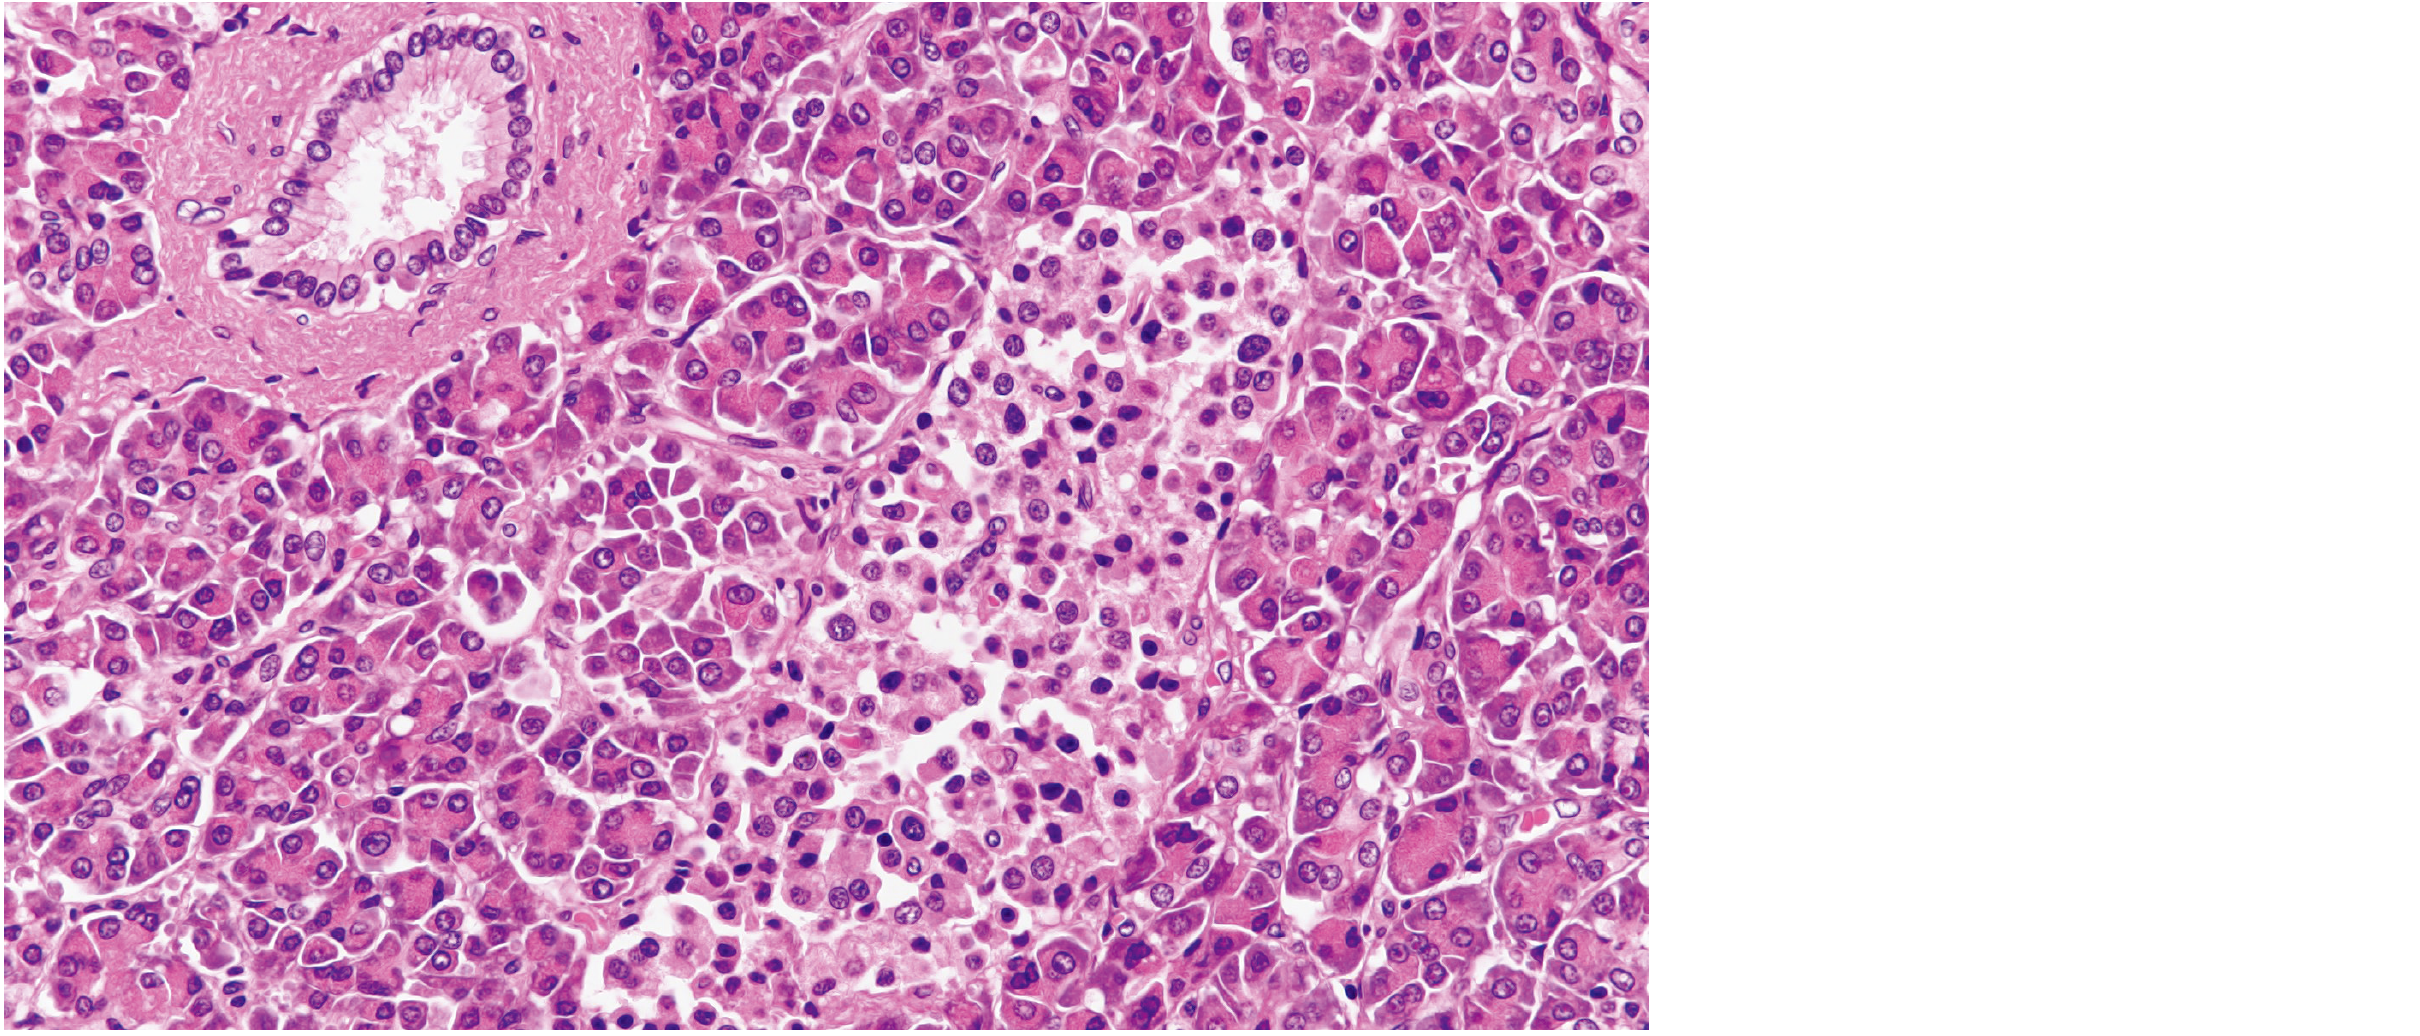

病理組織細胞学

(1.解剖学総論)

H-E 染色標本を示す。

臓器はどれか。

1. 肝 臓

2. 腎 臓

3. 膵 臓

4. 脾 臓

5. 副 腎

次へ